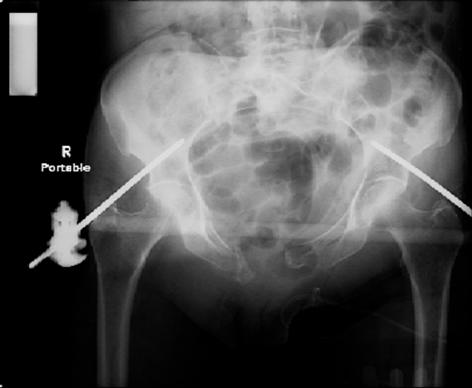

attached are images of a 70 year old female after peds versus car. her own car ran her over.

injuries are limited to the pelvis. left rami open and visible in a 10cm vertical laceration just lateral to left labia majora. wound is grossly clean. no vaginal and no urinary issues. CT scan shows widening of both SI joints anteriorly but I think this is vertically stable pattern.

pt treated that night with I/D and supra-acetabular frame to close the ring. consideration was given for SI screws bilateraly, but given time of night and other factors decision made not to proceed.

so the question is what next operatively if anything? concerns are infection, nonunion anteriorly and possible incompetence of the pelvic floor which may lead to prolapse issues. right rami are comminuted and plating may entail ilioinguinal approach to extend plate laterally to right iliac wing. retrograde screw up right rami is an option but I am not convinced it will add much. adding SI screws very doable, but major concern is restoring anterior ring. so far wound is clean and closed over a drain, and I have no plans to open it back up and wash again.

maintaining pelvic alignment in ex-fix in 70 yo female for any length of time may be challenging.

any thoughts? would anyone plate the pubic symphysis to close the gap and leave the more lateral rami fractures alone? the most recent pelvic case on this website involved pts with suprapubic catheters and antibiotic options including resorbable beads. I wonder how many people would plate and place antibiotic beads. thanks.

attached are several CT cuts. please let me know if you need more. the CT is pre-pelvic ex-fix placement.

Thank you.

Отправитель: Chip Routt 12 Июнь 2007, 04:53

I wouldn't plate the front.

But I would add screws posteriorly.